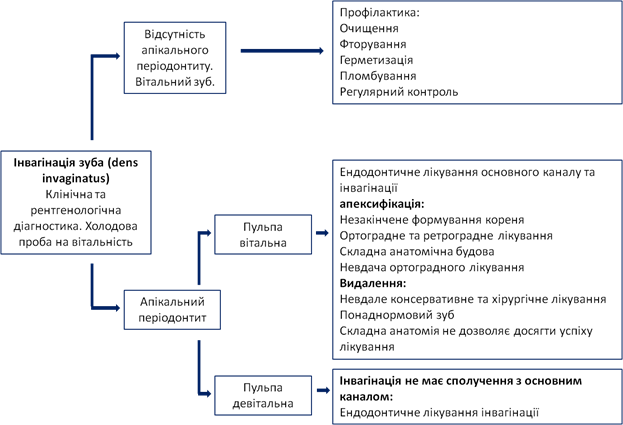

Ендодонтичне лікування зуба з інвагінацією є досить складним через складність будови кореневих каналів. До початку лікування необхідно провести повну діагностику. У випадку інвагінації третього типу можливий різний стан тканин пульпи: у інвагінації може спостерігатися некротичний розпад у той час як пульпа зуба в основному каналі може залишатися вітальною. Якщо це так, то зуб не потребує ендодонтичного лікування. Холодовий тест, у такому випадку, буде позитивний, не зважаючи на те, що тканини в каналі інвагінації можуть бути некротизовані, а на рентгенограмі присутні ознаки апікального періодонтиту.

Для обрання тактики лікування, при наявності інвагінації, ми керувались схемою Hülsmann (див. схема 2).